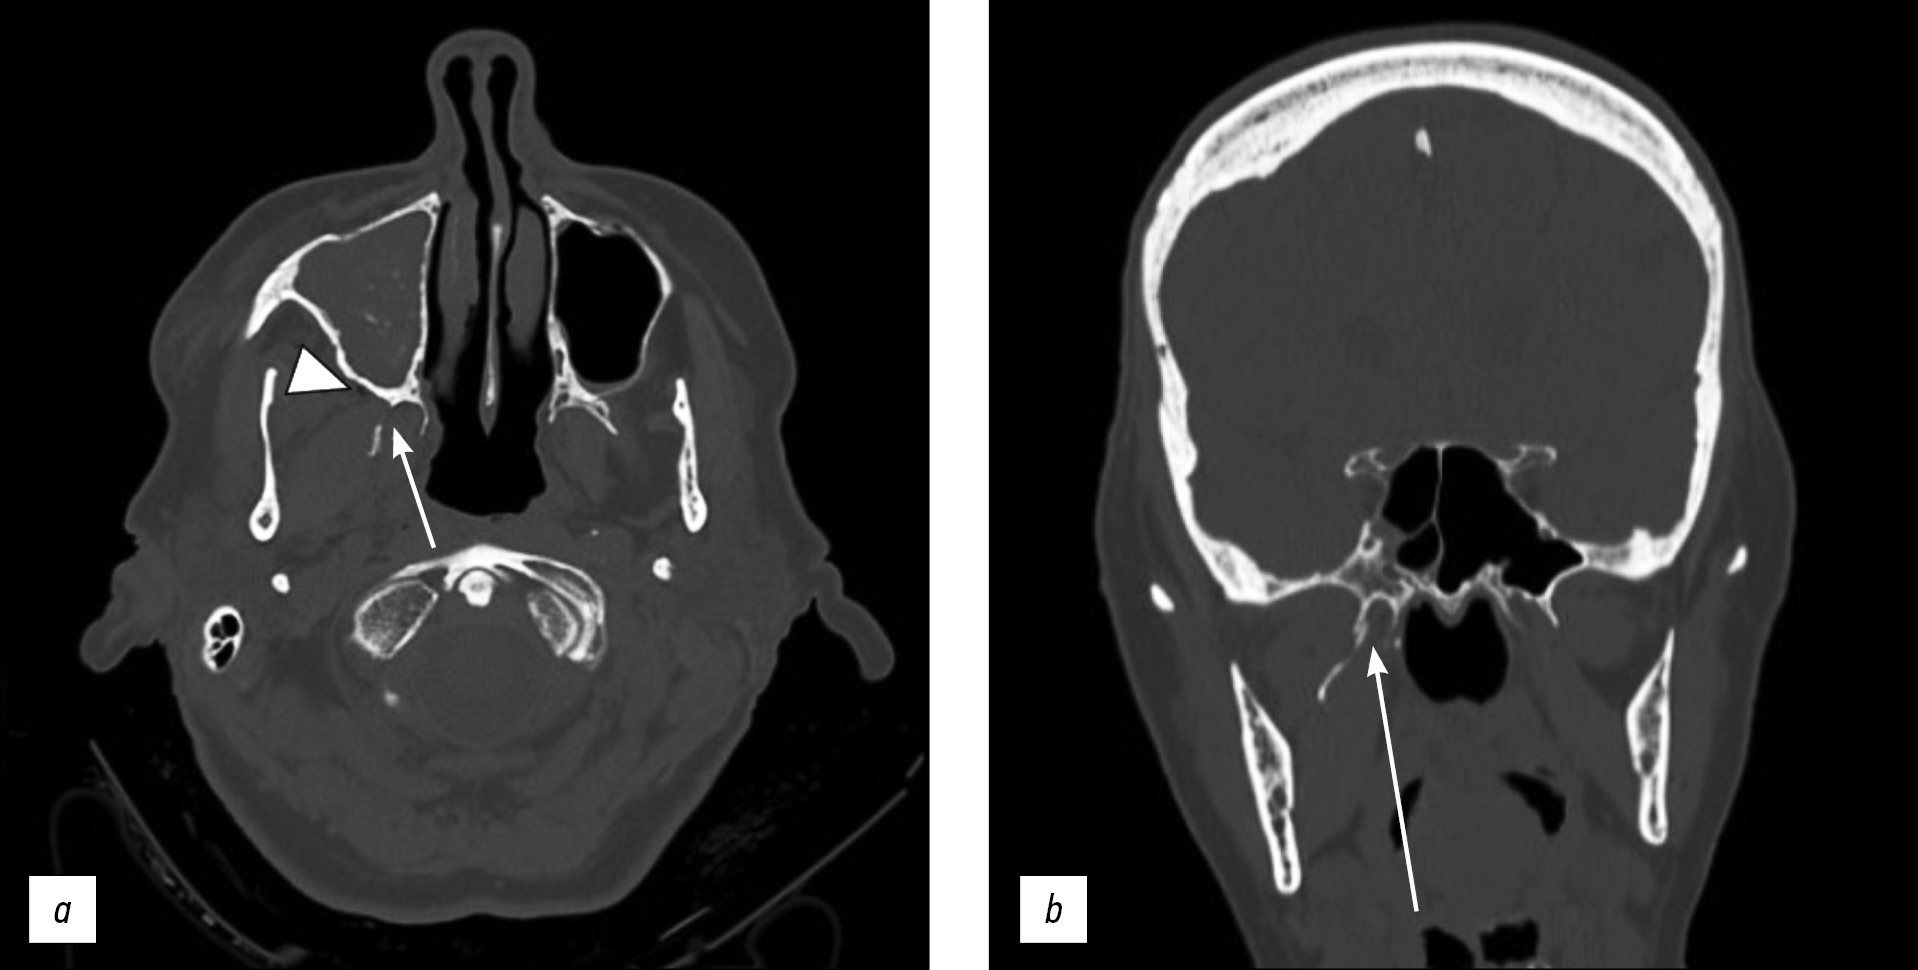

В статье описывается редкий случай изолированного одностороннего перелома крыловидного отростка у 71-летней пациентки с черепно-мозговой травмой и гематомой у основания правой глазницы, полученными в результате потери сознания.

Компьютерная томография показала односторонний перелом пластинки крыловидного отростка справа с признаками эмфиземы в жевательно-челюстном пространстве с ипсилатеральной стороны. Кроме того, у пациентки выявлен перелом медиальной стенки вехрнечелюстной пазухи справа с признаками гемосинуса. Переломы основания черепа или повреждения твёрдой мозговой оболочки не обнаружены. Пациентка получала консервативное лечение.